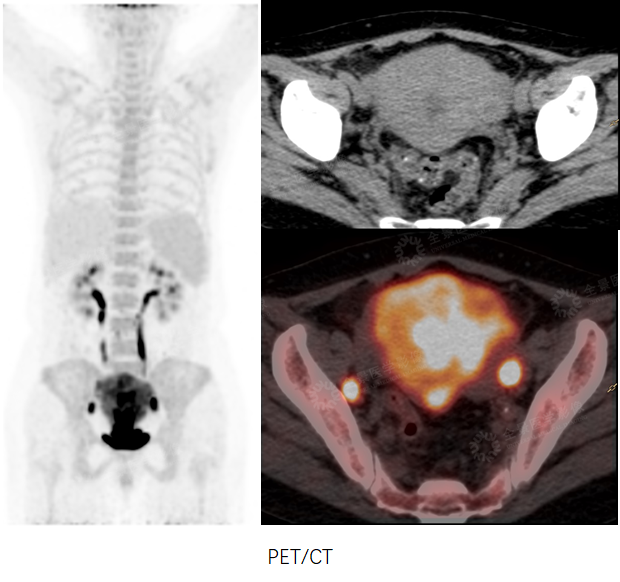

妇科

案例1 :女性,46岁,下腹部不适1周,CA125:791 u/ml↑。

PET/CT示盆腔内占位,由于PET/CT软组织分辨率有限,无法准确定位。MR增强示双侧卵巢显示不清,盆腔占位,考虑卵巢来源,性质待定。

PET/CT-MR融合,综合二者信息,考虑卵巢来源的恶性肿瘤。

术后病理:卵巢高分化浆液性癌

案例2 :女性,72岁,尿频1年余,CEA:214.1 ng/ml↑ ,CA125:56.97 u/ml↑。

PET/CT示盆腔内囊性肿物伴壁结节,壁结节FDG摄取增高。MR增强示左侧卵巢囊性肿物伴壁结节,性质待定。

PET/CT-MR融合示左侧卵巢囊性肿物伴壁结节,壁结节FDG摄取增高。

术后病理:左侧卵巢浆液性囊腺癌

案例3:女性,55岁,确诊“子宫内膜样腺癌”。

PET/CT术前评估,提示“双侧髂血管旁多发转移性淋巴结。但由于PET/CT软组织分辨率有限,无法提供肿瘤局部浸润深度信息,故行MR增强检查。

PET/CT-MR融合提示病灶侵犯肌层,双侧髂血管旁淋巴结转移,未见远处转移,提供了更为准确的临床分期。